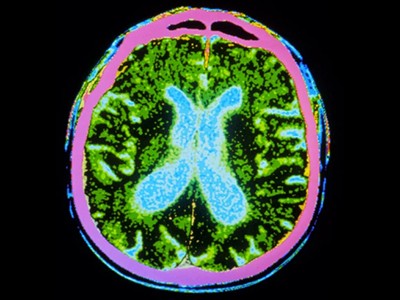

截至去年12月,共有83種源自多能干細(xì)胞的產(chǎn)品正在進(jìn)行115項(xiàng)臨床試驗(yàn)。帕金森病的治療方法比任何其他中樞神經(jīng)系統(tǒng)疾病的治療方法都處于更先進(jìn)的發(fā)展階段。帕金森病的特征是釋放神經(jīng)遞質(zhì)分子多巴胺的神經(jīng)元逐漸喪失。帕金森病相關(guān)的運(yùn)動(dòng)癥狀,例如肌肉僵硬、運(yùn)動(dòng)遲緩、震顫和步態(tài)障礙,都是由中腦黑質(zhì)區(qū)域神經(jīng)元的耗竭引起的。

帕金森病是由于大腦中釋放多巴胺(多巴胺能)神經(jīng)元逐漸喪失所致。Sawamoto 等人1和 Tabar 等人2進(jìn)行了一項(xiàng)基于干細(xì)胞治療的臨床試驗(yàn)。兩個(gè)團(tuán)隊(duì)都使用了臨床級(jí)多能干細(xì)胞來補(bǔ)充多巴胺能神經(jīng)元,這種細(xì)胞可以無限分裂并分化為任何細(xì)胞類型。Sawamoto等人使用了源自健康成年捐贈(zèng)者細(xì)胞的誘導(dǎo)多能干細(xì)胞系,而Tabar等人使用了源自早期胚胎的人類胚胎干細(xì)胞系。干細(xì)胞經(jīng)過培養(yǎng),形成多巴胺能神經(jīng)元祖細(xì)胞。這些細(xì)胞被移植到稱為殼核的大腦區(qū)域,殼核與尾狀核一起形成紋狀體。紋狀體與黑質(zhì)相連,而黑質(zhì)是多巴胺能神經(jīng)元損失最為嚴(yán)重的部位。早期(I/II期)臨床試驗(yàn)主要證實(shí)了該療法的安全性,同時(shí)也表明其在改善癥狀方面具有一定有效性。